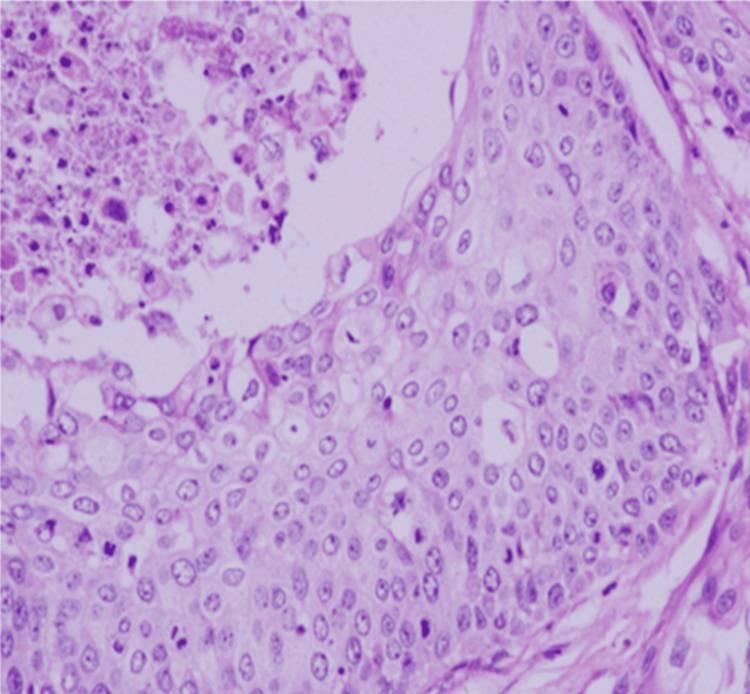

切除壁的组织病理学检查显示,乳头、小叶、片状和巢状结构中有高度细胞化的上皮生长。肿瘤表现出侵袭性特征,多边形细胞表现出多形性泡状核和中等细胞质。观察到角蛋白珠形成和活跃有丝分裂的焦点区域。基质显示明显的坏死和透明化,间质间隙有明显的淋巴细胞浸润(图5)。免疫组织化学分析显示,角蛋白呈阳性,CK呈局灶性阳性,CK20呈阴性(图(图6)。

图5 切除壁的组织病理学特征;呈片状组织的高度细胞性和侵袭性上皮肿瘤(苏木精和伊红染色)